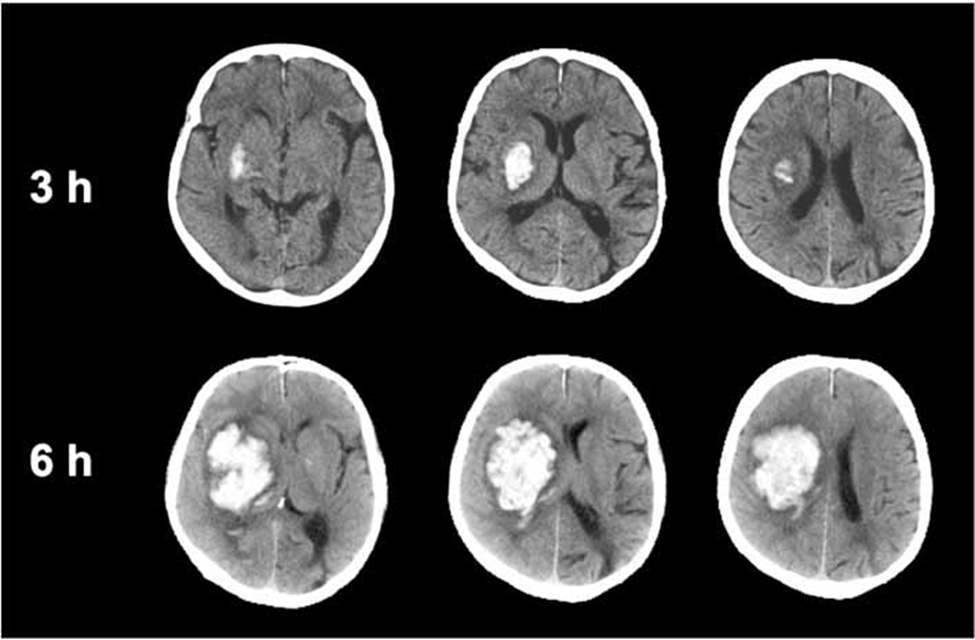

5/ Xuất huyết trong nhu mô não

Xuất huyết trong nhu mô não là tình trạng máu chảy trực tiếp vào mô não, tạo thành một khối máu tụ nằm trong nhu mô [1]. Khác với các loại xuất huyết khác xảy ra ở các khoang như ngoài màng cứng, dưới màng cứng hay dưới nhện, trong trường hợp này máu nằm ngay trong tổ chức não, gây phá hủy trực tiếp các tế bào thần kinh xung quanh. Đồng thời, khối máu tụ còn chiếm chỗ trong hộp sọ, làm tăng áp lực nội sọ và chèn ép các cấu trúc não lân cận, có thể dẫn đến phù não và lệch đường giữa nếu kích thước lớn.

Về cơ chế bệnh sinh, nguyên nhân thường gặp nhất là tăng huyết áp mạn tính. Tình trạng tăng huyết áp kéo dài làm tổn thương thành các tiểu động mạch trong não, gây thoái hóa và hình thành các vi phình mạch [4]. Khi các mạch này vỡ, máu sẽ tràn vào nhu mô não. Các vị trí hay gặp bao gồm nhân xám trung ương như nhân bèo, đồi thị, bao trong, ngoài ra còn có thể gặp ở cầu não hoặc tiểu não. Bên cạnh đó, các nguyên nhân khác như dị dạng mạch máu (AVM), u não chảy máu, rối loạn đông máu hoặc chấn thương cũng có thể gây xuất huyết trong nhu mô, đặc biệt ở người trẻ [6].

Về lâm sàng, bệnh thường khởi phát đột ngột với các dấu thần kinh khu trú rõ rệt, phản ánh vị trí tổn thương trong não [2]. Bệnh nhân có thể xuất hiện yếu hoặc liệt nửa người, rối loạn ngôn ngữ (nói khó hoặc mất ngôn ngữ), méo miệng, rối loạn cảm giác hoặc mất thăng bằng. Kèm theo đó là các triệu chứng tăng áp lực nội sọ như đau đầu, buồn nôn, nôn và giảm mức độ ý thức. Trong các trường hợp nặng, bệnh nhân có thể nhanh chóng rơi vào hôn mê. Mức độ và biểu hiện cụ thể phụ thuộc vào vị trí và kích thước của ổ xuất huyết, cũng như mức độ phù não và chèn ép các cấu trúc quan trọng.

Nguồn: Bornes, T. D., & Butcher, K. Management of hypertension in the acute phase of stroke [Figure 3: Hematoma expansion]. ResearchGate